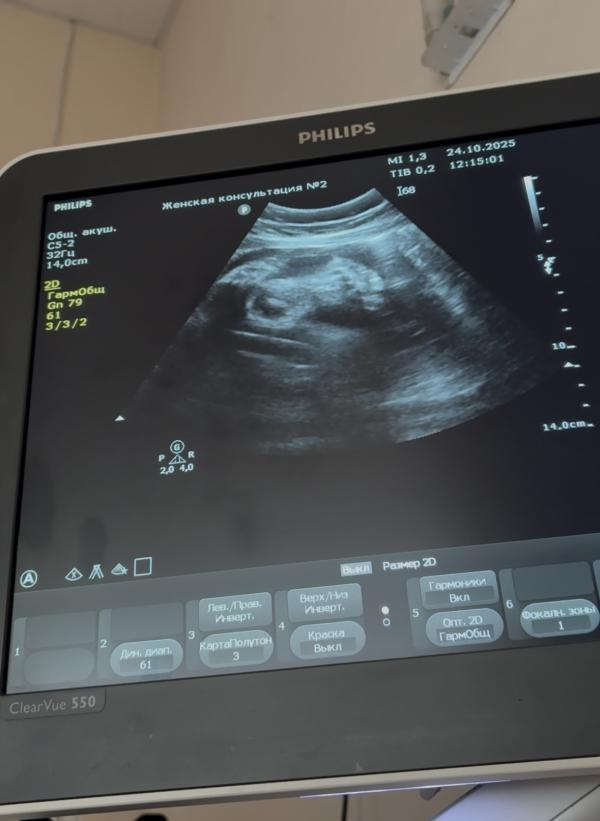

Сегодня была на 3 скрининге. Срок по календарю 34.1, по узи 35.5, голова дочки уже внизу 😅

Симфизита нет, немного размягчился хрящ. Кровотоки отличные. Активная, развиваемся с небольшим опережением 😊

*на фото ступня 7 см 😅